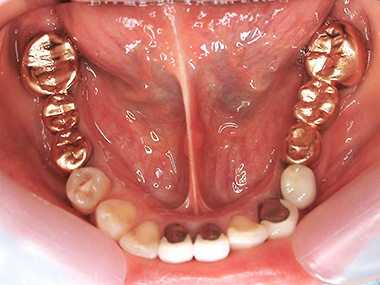

術前 上顎

4番はメタルボンド。

5〜7番はインプラントによる治療を行います。

術後 上顎

術前 下顎

右下5〜7番(写真左手)はインプラント治療を行います。

術後 下顎

術後 側面